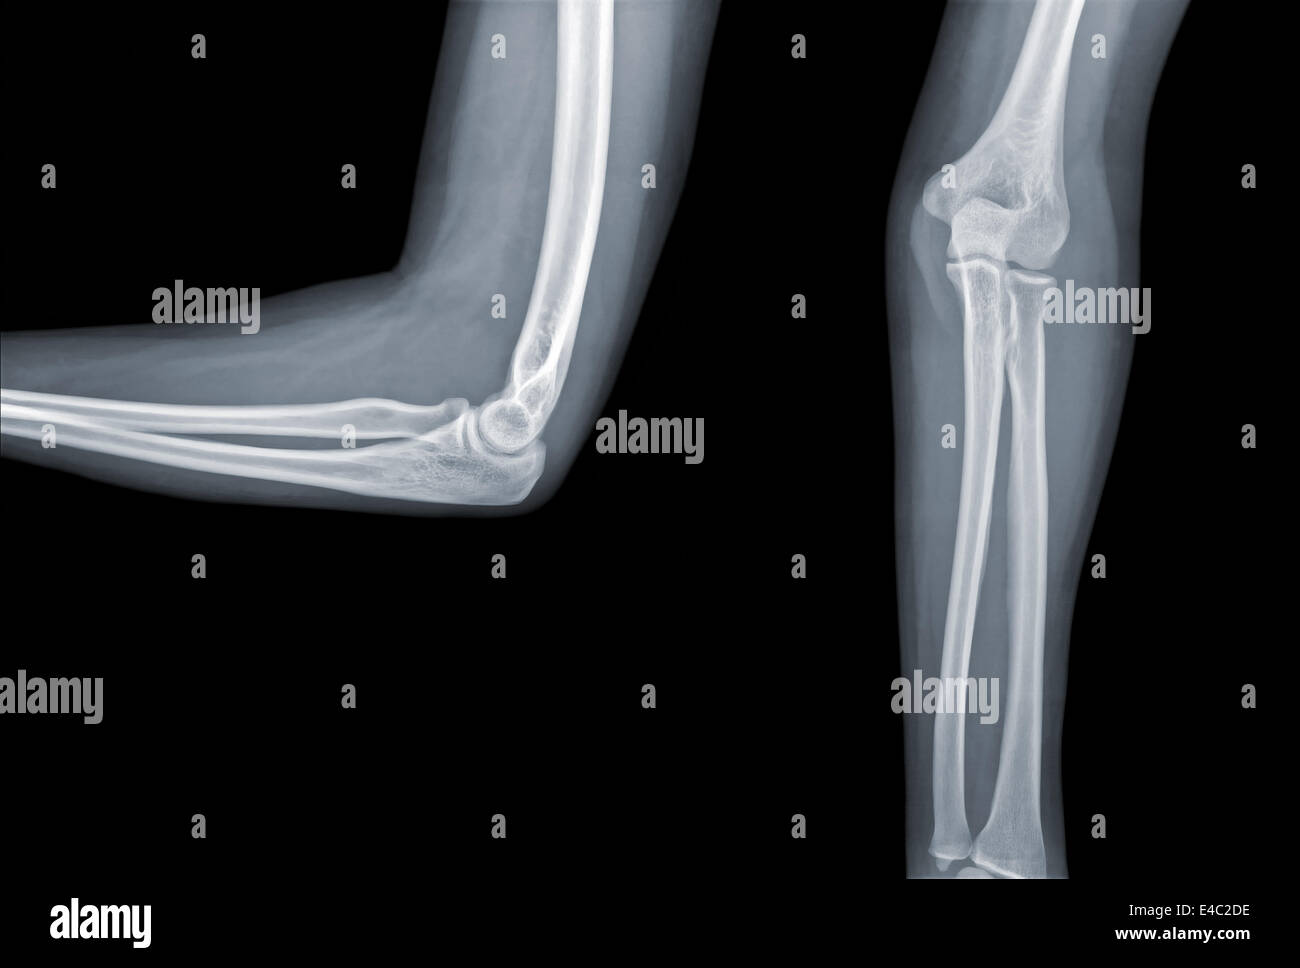

X Ray Elbow

Elbow x-ray - labelling questions | Radiology Case | Radiopaedia.org Anatomy of Elbow X-rays - YouTube Elbow series | Radiology Reference Article | Radiopaedia.org EMRad: Radiologic Approach to the Pediatric Traumatic Elbow X-ray | X Ray Elbow